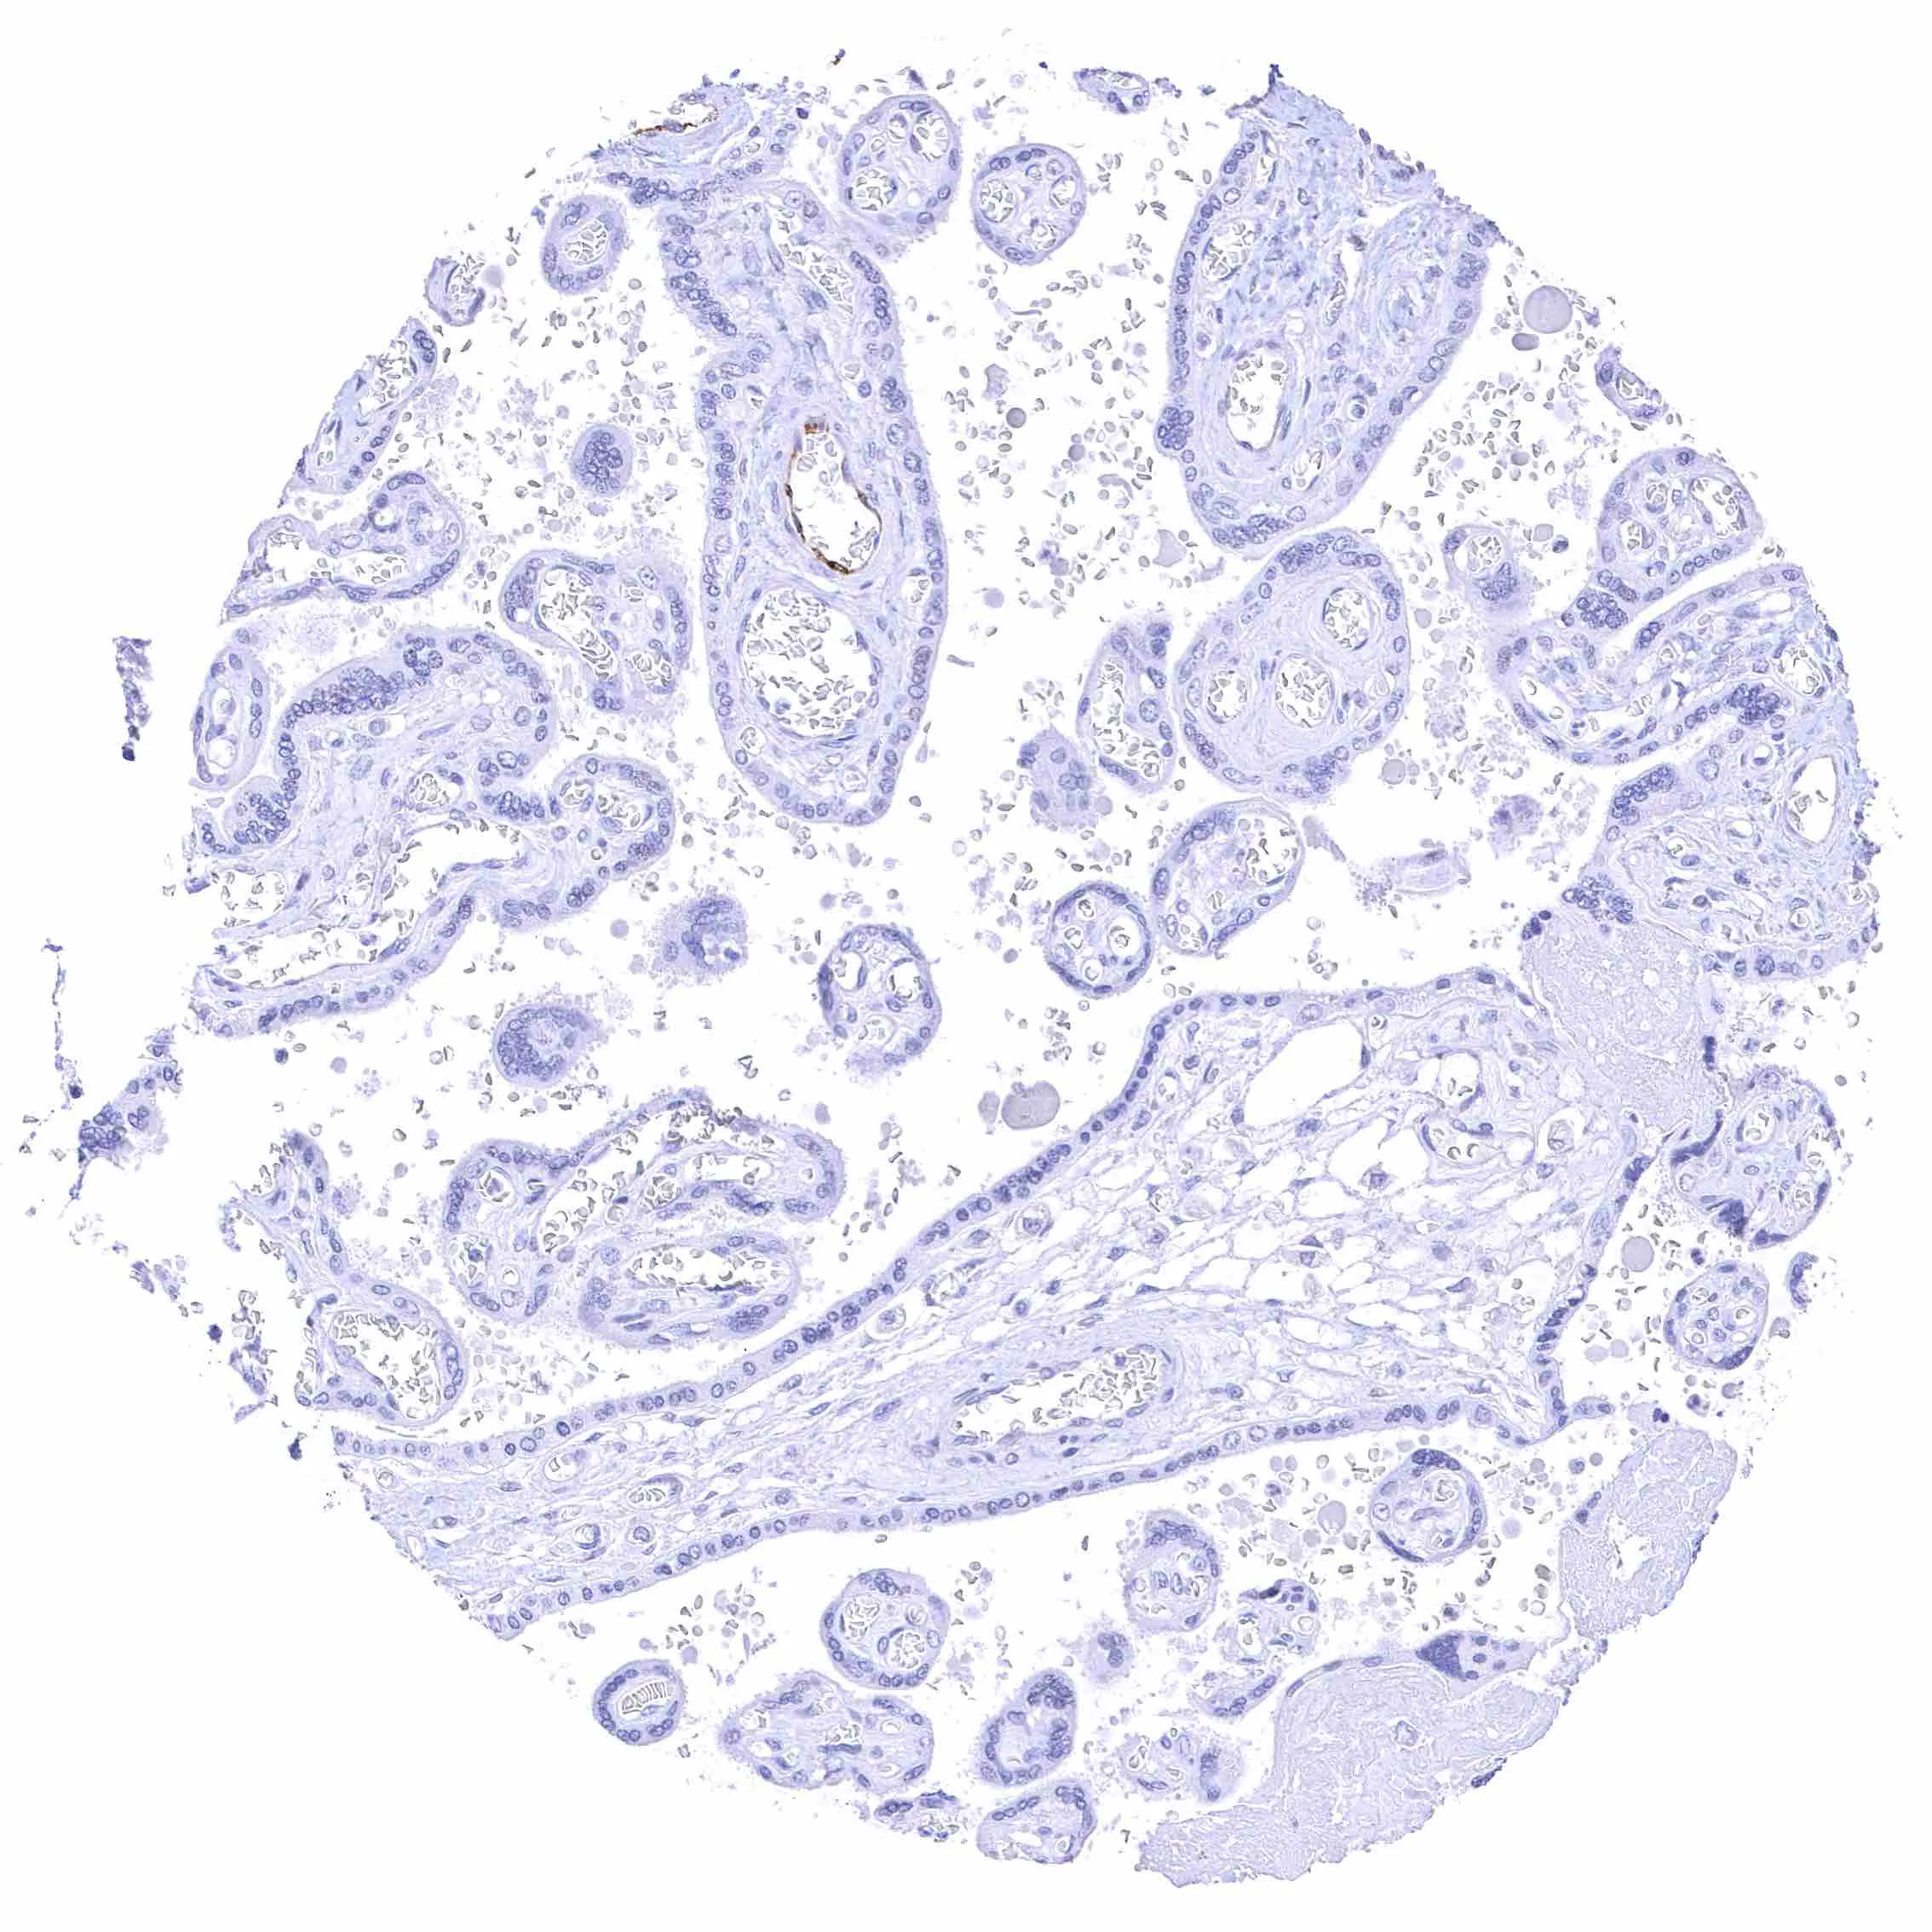

Kidney, cortex – Distinct membranous NPR-C staining at the luminal cell border of a subset of tubuli, the parietal membrane of the Bowman capsule, and in glomerular endothelial cells.

Kidney, cortex – Distinct membranous NPR-C staining at the luminal cell border of a subset of tubuli, the parietal layer of the Bowman capsule, and in glomerular endothelial cells.